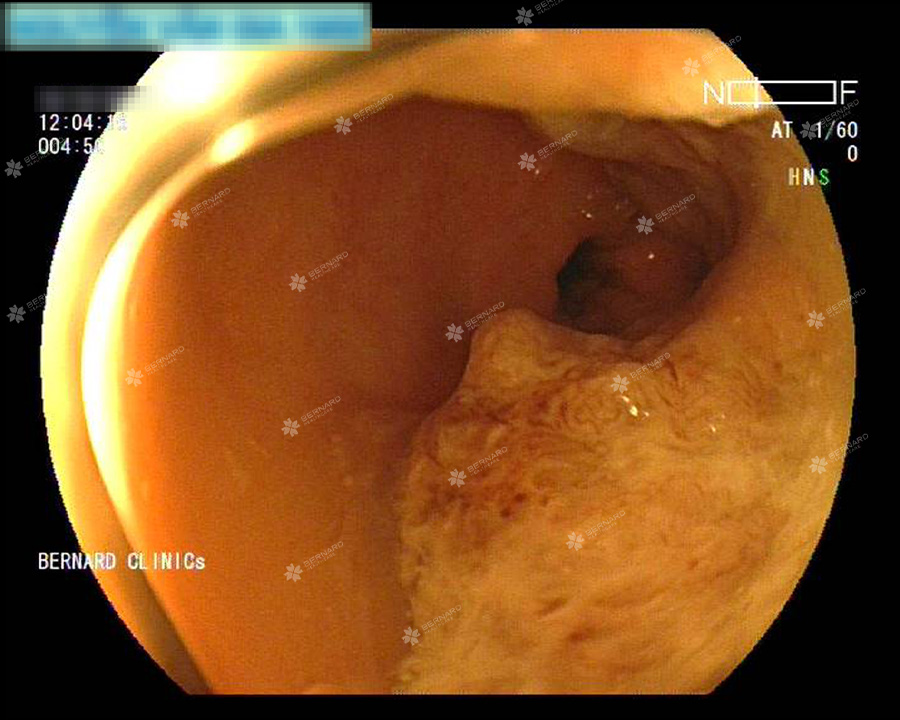

Tại đại tràng trái cách hậu môn nhân tạo 8cm có tổn thương u sùi gây hẹp lòng, nghi ung thư mới. Giải phẫu bệnh xác nhận cả hai vị trí đều là ung thư.